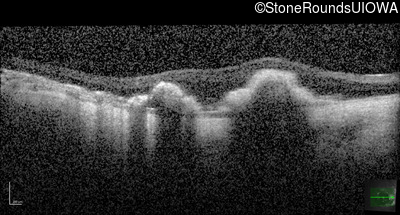

Optical Coherence Tomography - Right - Count Fingers 6'

Exemplar / OCT Stack